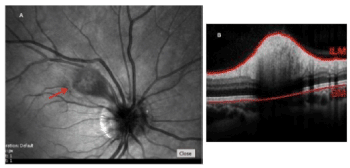

The patient was referred to our Retina clinic the next day for further evaluation. Spectral-Domain OCT at the level of the right cotton-wool spot revealed increased retinal nerve fiber layer thickness (Figure 2). Given the funduscopic appearance of the optic discs, further assessment with orbital ultrasound was performed, which revealed a few buried optic disc drusen bilaterally. Blood workup included the following: complete blood count, blood glucose, antinuclear antibody (ANA) titer, HIV and syphilis serology, Bartonella Hensalae IgG-IgM, CMV IgG-IgM, Zika virus IgM titer (given the patient’s trip to Puerto Rico during the Zika virus epidemic). Lyme disease antibody test was not ordered due to documented negative titers. The patient maintained full visual acuity in each eye, and no treatment was initiated. The blood workup was negative, except for a mild elevation of the ANA titer (1:40). Therefore, the patient was referred to Rheumatology: she did not meet the diagnostic criteria for SLE, and the presence of other autoimmune/rheumatologic disease was ruled out. There was no indication for initiation of medical treatment, and the patient continued to be managed conservatively by close observation only.

Figure 2. Right eye cotton-wool spot appearance on infrared imaging (A, arrow), and corresponding cross-sectional Spectral-Domain OCT scan across the cotton-wool spot (B) showing increased retinal nerve fiber thickness (total retinal thickness: 521 µm).